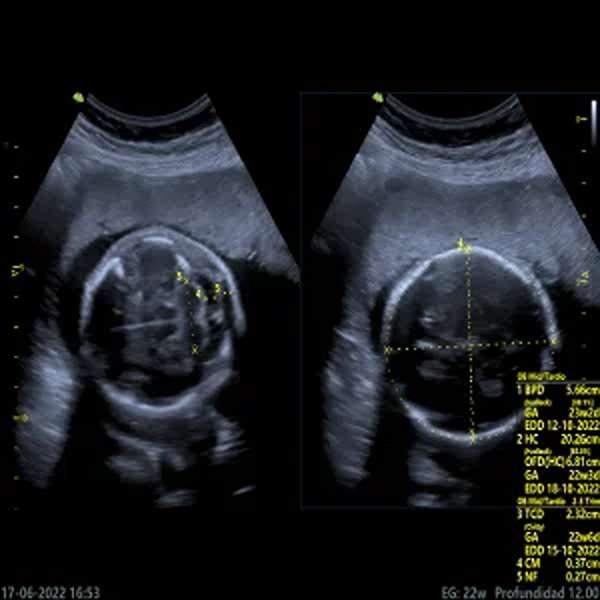

La ecografía morfológica es un estudio detallado que se realiza entre las semanas 18 y 24 de embarazo para evaluar el desarrollo anatómico del feto. Permite examinar órganos, extremidades, columna, corazón y cerebro, detectando posibles malformaciones congénitas. También analiza la placenta, el líquido amniótico y el cordón umbilical, asegurando un adecuado crecimiento del bebé. Es un procedimiento seguro e indoloro, fundamental en el control prenatal para identificar anomalías y planificar intervenciones médicas si es necesario.

Ecografía Morfológica 3D | 4D